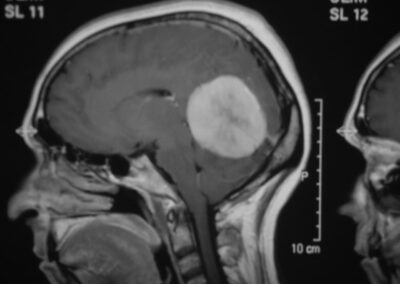

El diagnóstico se puede confirmar y el tumor localizar mediante:

• TAC cerebral

• RM cerebral

• Angiografía cerebral